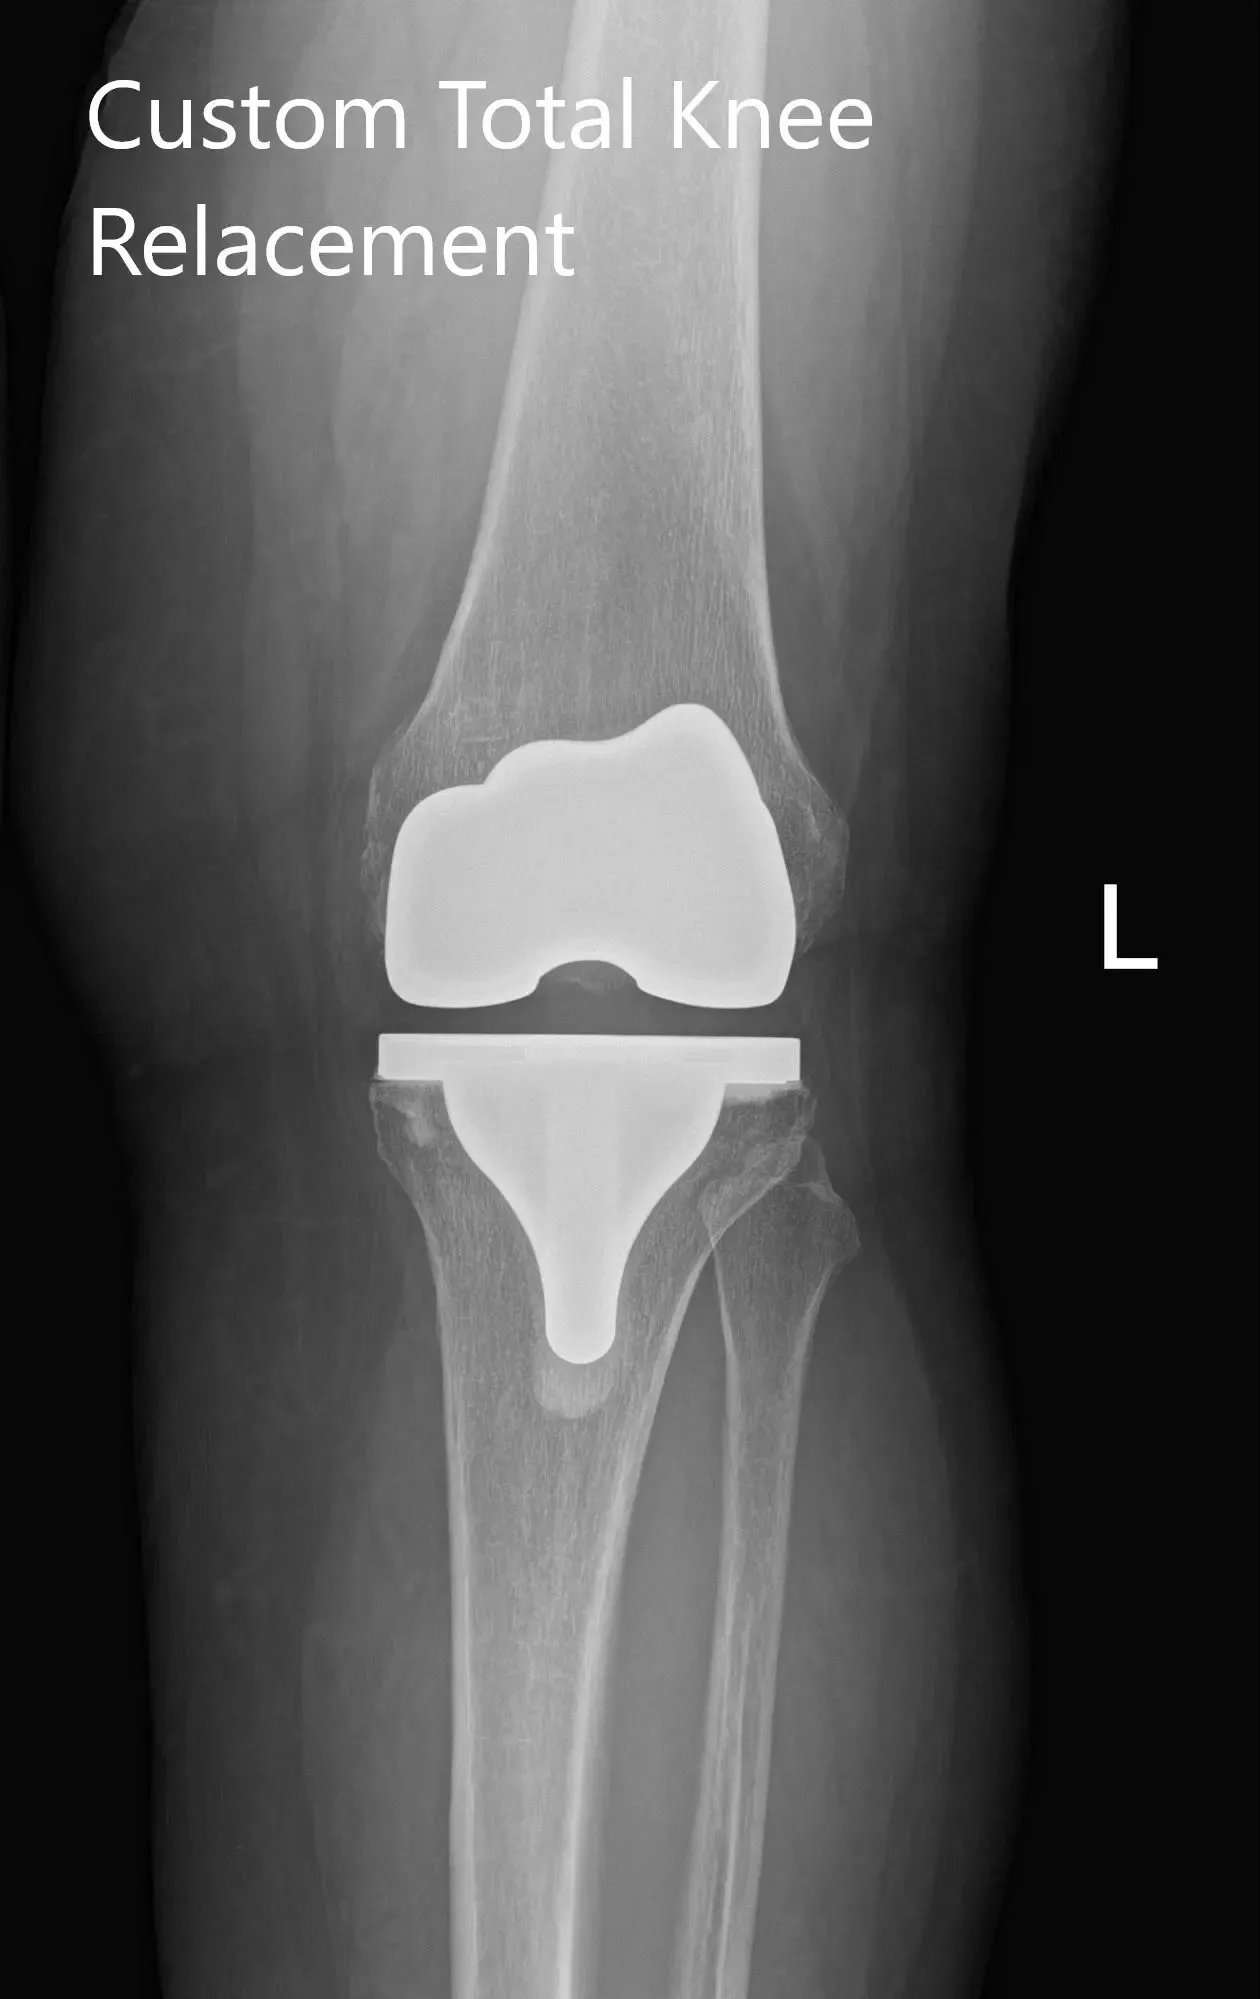

Radiografía postoperatoria de la rodilla izquierda que muestra visión AP y lateral